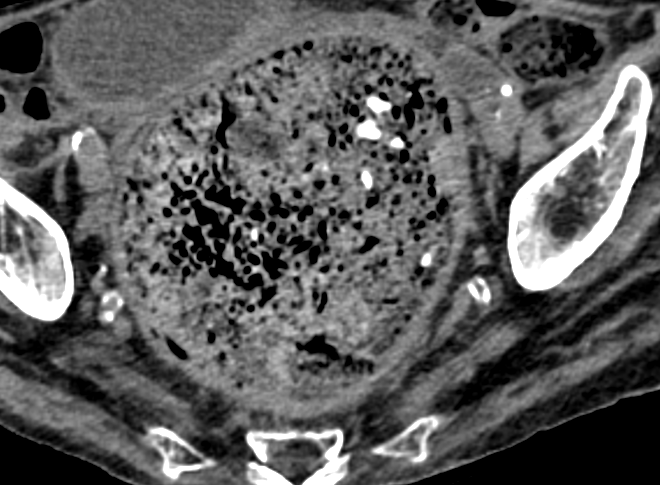

• Risque de Colite Stercorale

CT

• Ne pas confondre avec la vessie !

Entrainant une ischémie

facalome fecalome faecal fécal fecal fecaloma